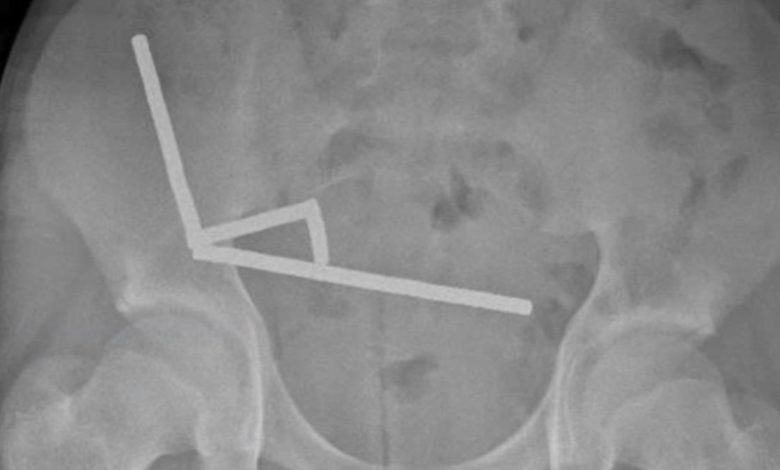

Рентгеновский снимок показал наличие четырех линейных цепочек в разных отделах кишечника пациента. Оказавшись внутри, небольшие металлические предметы соединились разрушительным образом. В ходе операции было установлено, что цепочки находились в отдельных участках тонкой кишки и слепой кишки. Сжимаясь, они вызвали отмирание нескольких участков ткани из-за недостатка кровоснабжения, известное как давление-некроз.